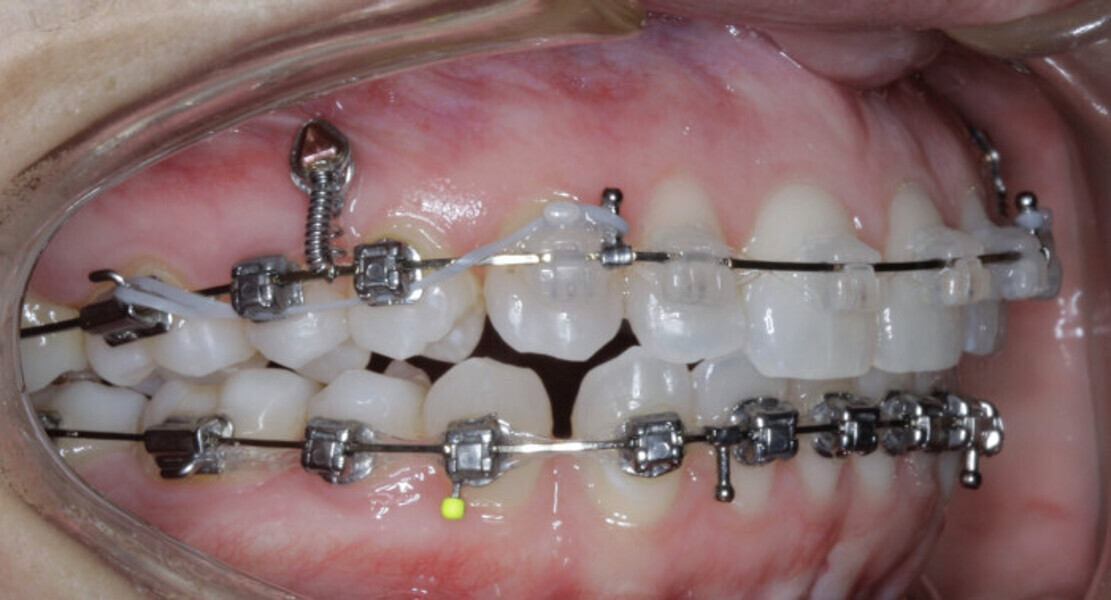

New Age orthodontics and orthopaedics with temporary anchorage devices